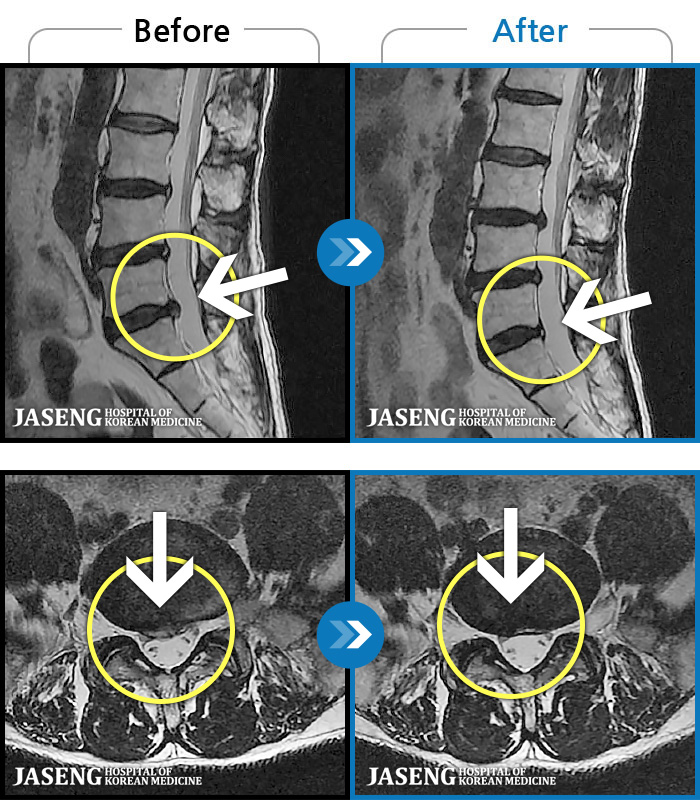

1,240 MRI ũ ʸ Ȯϼ.

| [뱸] 19.11.28~25.05.06